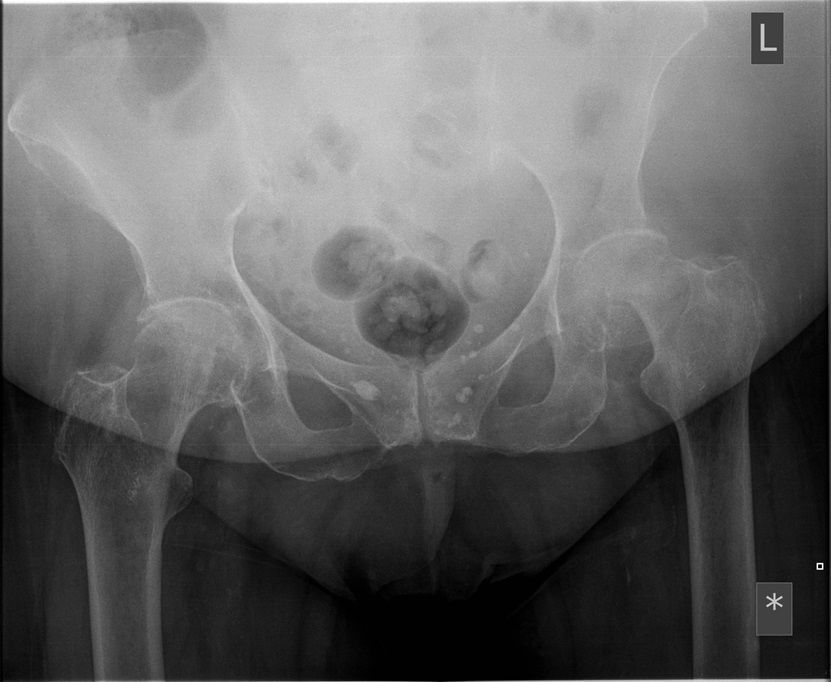

Question 4

Question

Which operation would you perform?

Answer

• THR

• Hemiarthroplasty